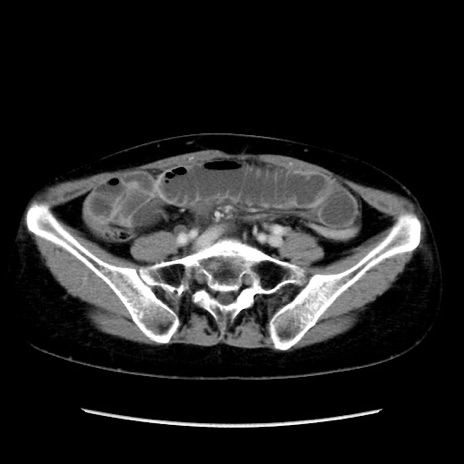

冠状断像

【症例】40歳代 女性

【主訴】上腹部痛、嘔気・嘔吐

【現病歴】約9時間前頃から急に上腹部痛、嘔気、嘔吐が出現。改善しないため救急要請。

【既往歴】子宮頚癌(広汎子宮全摘術、放射線療法)、腸閉塞

【身体所見】腹部:平坦、軟、腸雑音亢進、上腹部を中心に腹部全体に圧痛あり。

【データ】WBC 8400、CRP 0.03